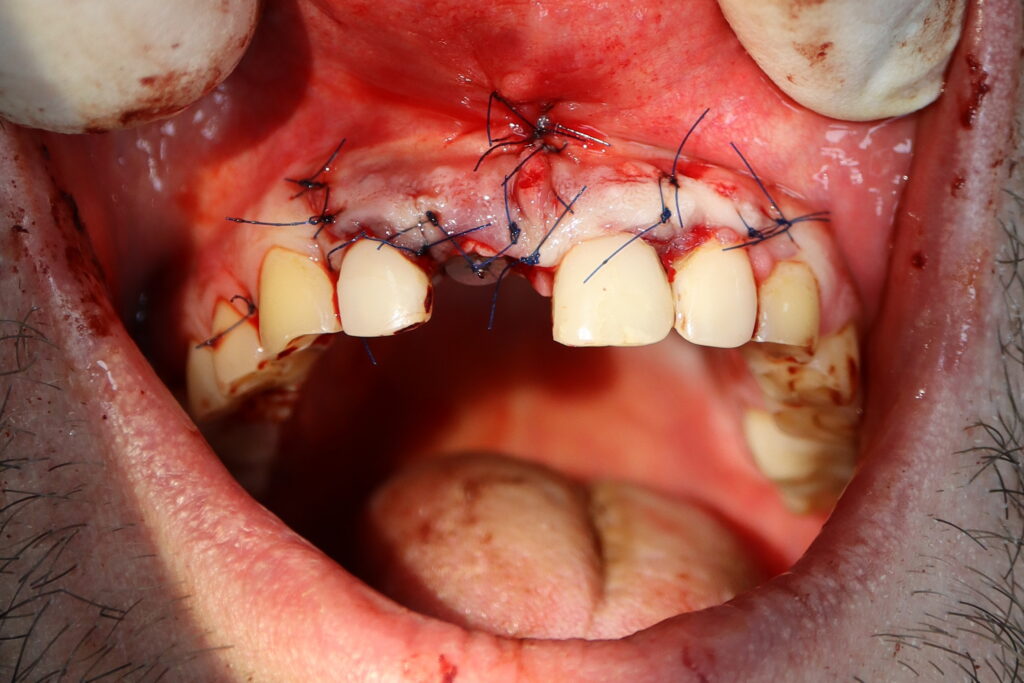

Процесс работы

Что было сделано:

Хирургом-имплантологом были проведены следующие манипуляции: удаление зуба 1.1, удаление кисты, аугментация твердых и мягких тканей в области 1.1

с применением свободного соединительнотканного трансплантата из слизистой оболочки бугра верхней челюсти, пластика уздечки верхней губы.

Установлен имплантат Straumann BLT и формирователь десны.

В этот же визит терапевтом был изготовлен адгезивный протез для устранения эстетического дефекта до момента остеоинтеграции имплантата.

Постоянная коронка будет установлена спустя 3 месяца.

удаление зуба

Это фото может содержать тяжелый для восприятия контент